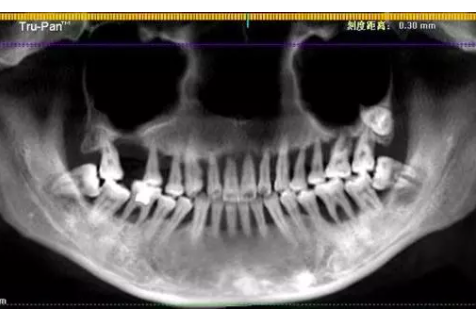

二、牙片中清晰可见小萌的上口牙已摇摇欲坠

6年时间从轻度到重度牙周炎,牙龈出血或红肿万不可小觑

医生说,导致小萌半口多牙松动至功能丧失的是重度牙周炎。牙周炎是种人人都可能遇上的牙周支持组织的慢性炎症,一般从局部发生开始,比如常见的刷牙时出血、牙龈红肿等,若不及时治疗可蔓延至全口牙,同时炎症也会从表面的牙龈深入到牙骨,从牙根上进行破坏。

就拿小萌来说,其实在6年前已出现有两颗牙齿松动,当时她也上医院看过,医生告知这是牙周炎得系统治,她用了点消炎药后牙龈肿痛的症状消失了也就没当回事。直到6年后门牙脱落再就诊,牙龈和牙槽骨严重萎缩,牙根都暴露在外面,给后续的种牙也增添了不少的难度。

在看过小萌令人震惊的牙片之后,细心的人肯定已经注意到,这姑娘的全口牙虽已不同程度的松动,却没有一颗蛀牙。而众所周知,口腔卫生不好也是导致蛀牙的主要原因之一,那么为什么口腔卫生糟到患重度牙周炎的小萌至今不蛀牙呢?